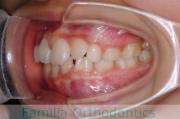

No.19V-044

- 上顎前突

- 13歳

- 女性

- 上:

- 44

- 下:

- 8558

- 主な使用装置:

- FEA

- 治療にかかった費用:

- 85万円

出っ歯を治したいということで小学生の時に来院されました。中学生になるまで経過観察をして、診断、上下左右から小臼歯を抜歯してマルチブラケット法にて治療を行いました。2年強、30回程度の通院が必要でした。

口元の突出感も大きく改善しています。

- ≫治療前

- ≫治療後

上下とも前歯の叢生(でこぼこ、凹凸、ガタガタ)がありましたので、保定をしっかりやらないと後戻りのリスクが出てきます。